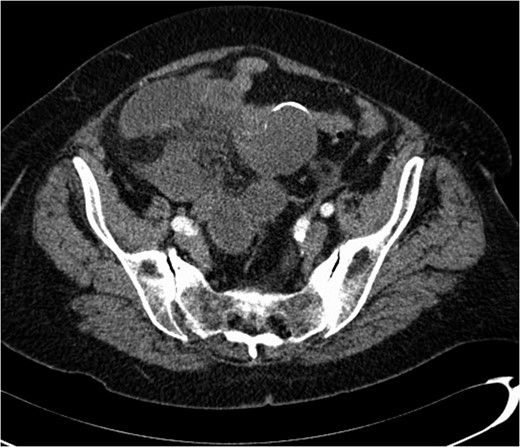

A 74-year-old female, with a background history of hypertension and hypothyroidism, presented to the emergency department with a 6-h history of sudden onset generalized abdominal pain. The pain was colicky in nature, associated with nausea and refractory to analgesia. Examination revealed tenderness in the right upper quadrant and epigastrium. Blood tests were normal except for a mild neutrophilia (7.5 × 109/l) and lactate of 2.5 mmol/l. A computed tomography (CT) scan of her abdomen and pelvis was performed which showed abnormal loops of small bowel along the right side of the abdomen with mesenteric fat stranding. A partially calcified structure was noted lying medial to the loops of bowel (Figs 1 and 2). The patient proceeded to have an explorative laparotomy performed. Intraoperative findings revealed an ischaemic loop of small bowel wrapped around a mass in the mesentery adjacent to the sigmoid colon (Fig. 3). The patient underwent a partial small bowel resection with primary anastomosis and en-bloc resection of the mass with the formation of an end colostomy. The final histological revealed a 6 × 4 × 4 cm cystic colonic duplication cyst separate but adjacent to the sigmoid colon. The inner lining of the cyst revealed mucinous epithelium, with mucin contained within. The wall of the cyst was sclerotic with occasional lymphoid aggregates, smooth muscle and neurovascular bundles (Fig. 4). The patient made a good recovery and was discharged home.

Coronal CT scan showing a partially calcified structure adjacent to loops of small bowel.